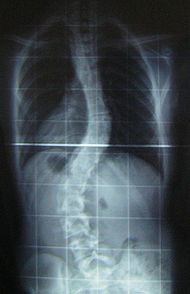

L'esame strumentale per eccellenza è la radiografia che viene fatta in toto sul rachide, in 2 proiezioni anteriore e laterale (a meno che non si supponga qualche altra patologia che indurrà a fare degli scatti anche in altre proiezioni). Si effettua una rx anche in posizione supina per escludere gli effetti della forza di gravità silla curva scoliotica.

L'interpretazione delle radiografie permette di classificare la scoliosi in base ai gradi di deviazione (Cobb) ed in base alla chiusura o meno dei nuclei di ossificazione delle cartilagini (Risser).

Dalle radiografie innanzitutto si può capire se trattasi di scoliosi vera (rotazione delle spinose vertebrali attorno all'asse longitudinale) oppure di una deviazione che laterale senza rotazione delle sponose.